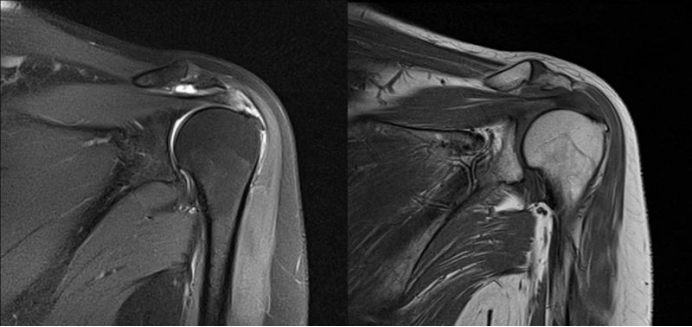

(4)MRI:行MRI检查出现肩关节韧带损伤、肿胀、撕裂可确诊;